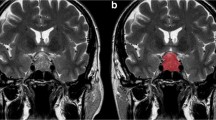

Two hundred forty-six pituitary adenoma patients (84 aggressive, 162 non-aggressive) who underwent preoperative MRI were retrospectively reviewed. The patients were divided into training (n = 193) and testing (n = 53) sets. Clinical information, shape-related, and textural features extracted from the tumor volume on contrast-enhanced T1-weighted images (CE-T1WI), were compared between aggressive and non-aggressive groups. Variables with significant differences were enrolled into Pearson’s correlation analysis to weaken multicollinearity. Logistic regression models based on the selected features were constructed to predict tumor aggressiveness under fivefold cross-validation.

Sixty-five imaging features, including five shape-related and sixty textural features, were extracted from volumetric CE-T1WI. Forty-seven features were significantly different between aggressive and non-aggressive groups (all p values < 0.05). After feature selection, four features (SHAPE_Sphericity, SHAPE_Compacity, DISCRETIZED_Q3, and DISCRETIZED_Kurtosis) were put into logistic regression analysis. Based on the combination of these features and Knosp grade, the model yielded an area under the curve value of 0.935, with a sensitivity of 94.4% and a specificity of 82.9%, to discriminate between aggressive and non-aggressive pituitary adenomas in the testing set.